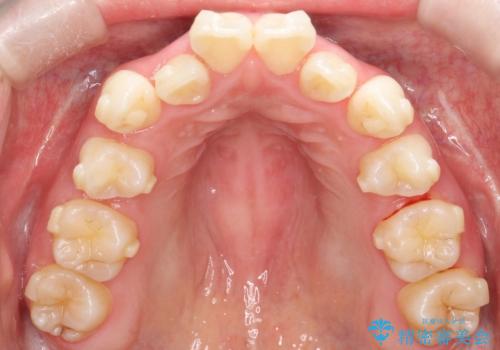

【抜歯インビザ】前歯の凸凹をなおしたい

- 前歯の凸凹を主訴に来院されました。

前歯はあまり下げる必要がなかったため、上下左右の第二小臼歯抜歯を行う治療計画としました。

途中、臼歯の近心傾斜を認めましたが、追加アライナーを使用することでリカバリーを行いながらインビザラインのみで治療を完了することができました。